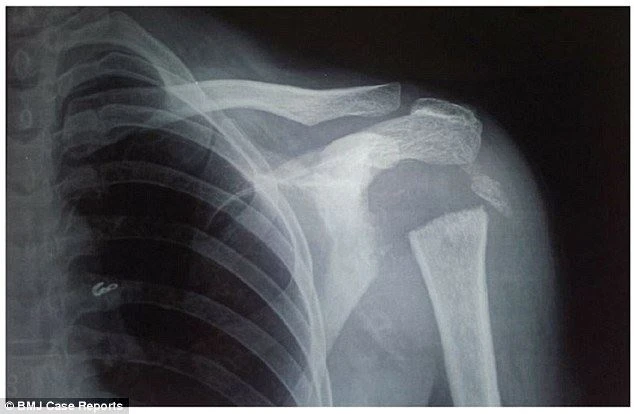

Các bác sĩ tại học viện Khoa học Y dược Pondicherry nhận thấy phần vai của cô mềm nhũn và cô có thể xoay tay 180 độ. Sau khi dùng tia X để kiểm tra, họ phát hiện phần đầu xương cánh tay của cô - phần xương hình tròn nối liền cánh tay và bả vai đã không còn.

Ảnh chụp X-quang cho thấy phần xương nối liền bả vai và cánh tay của cô đã không còn. Ảnh: BMJ Case Reports.